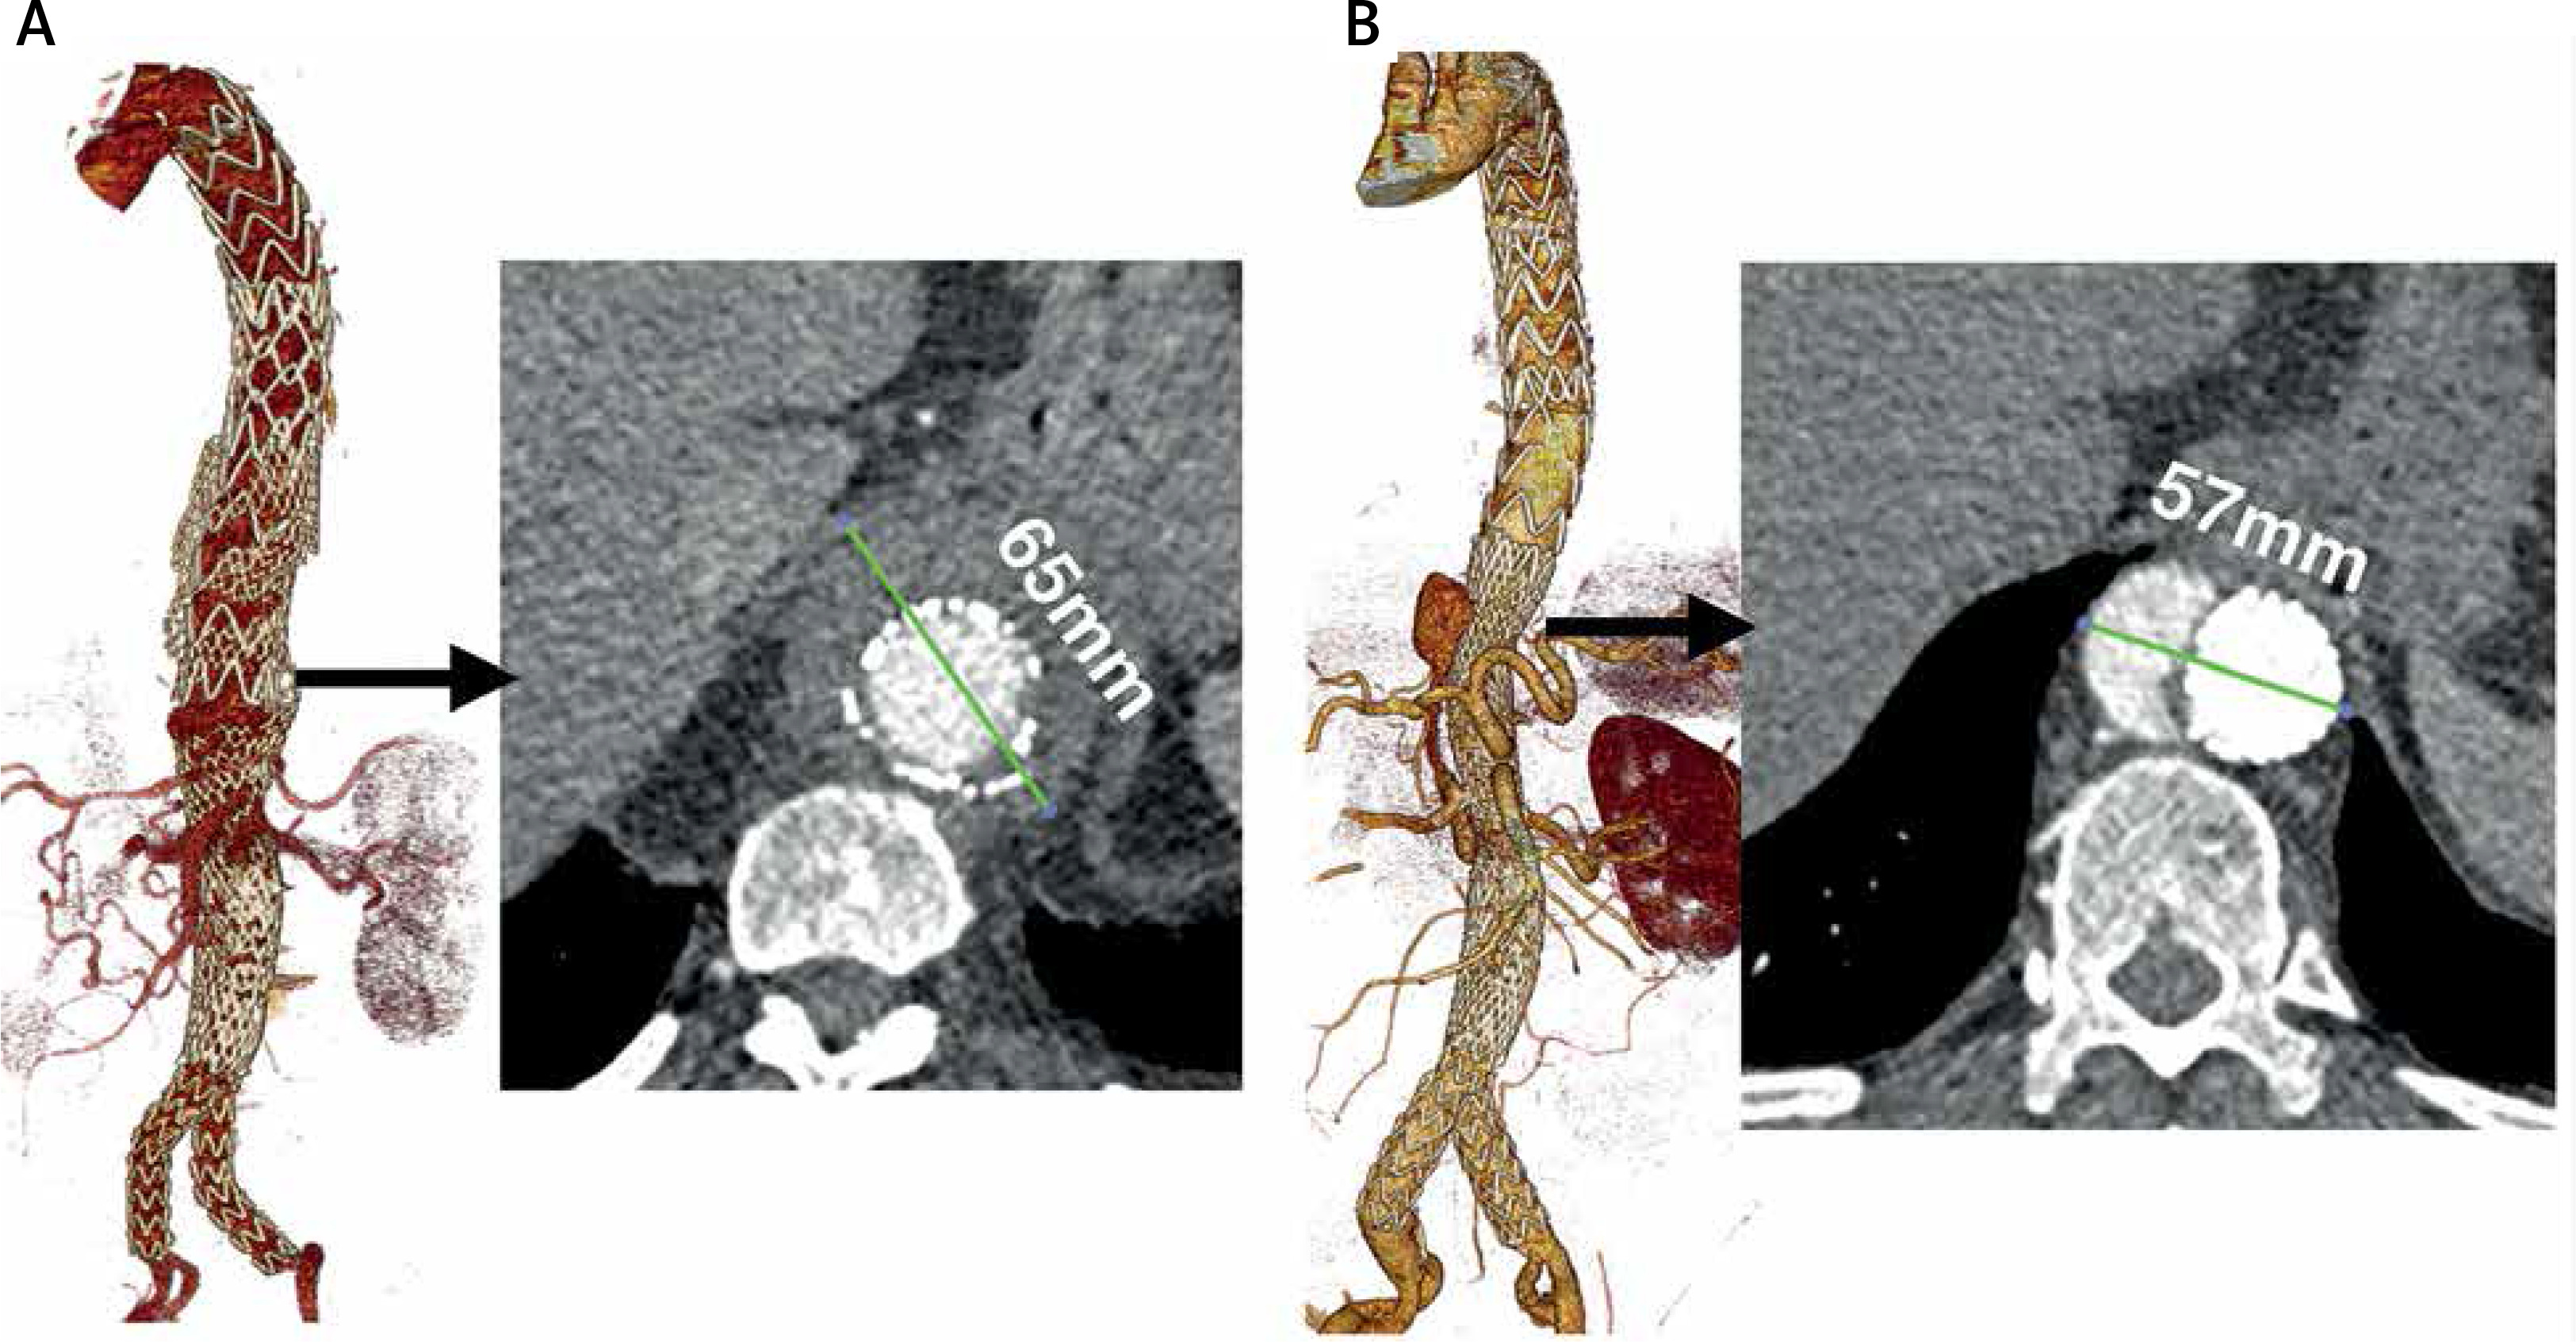

Figure 3

A – Aortic enlargement due to type V endoleak (sac extension) without false lumen perfusion. B – False lumen expansion due to entry from dissected right renal artery and impaired outflow. Values show total diameters of the aorta